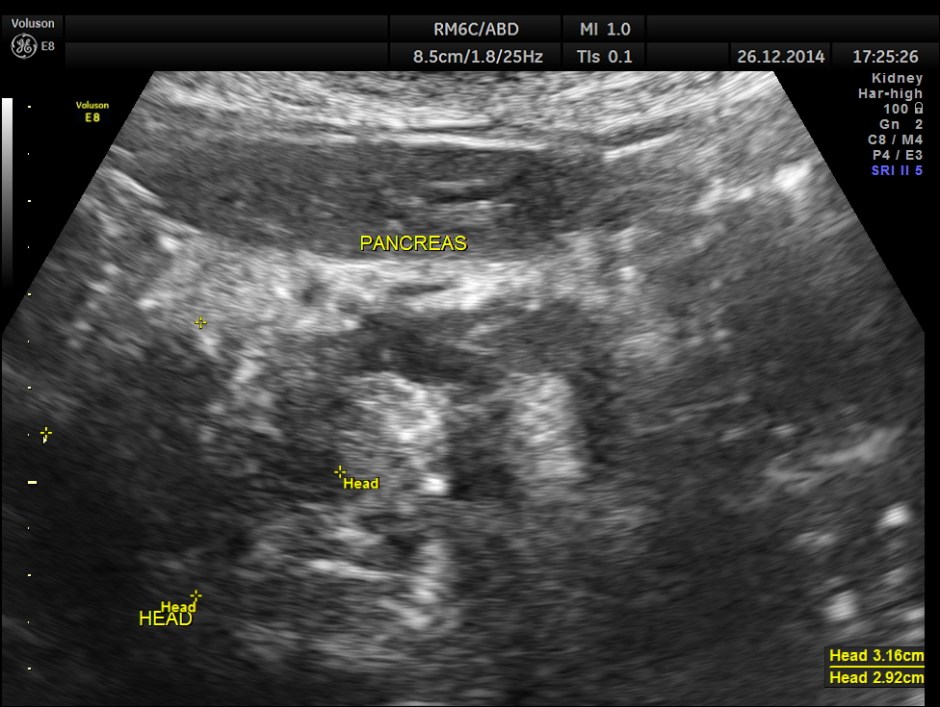

This was a 82 year old lady being evaluated for abdominal pain . Her serum bilirubin was very high and she was referred for an ultrasound .

the head region of the pancreas shows an irregular mass lesion